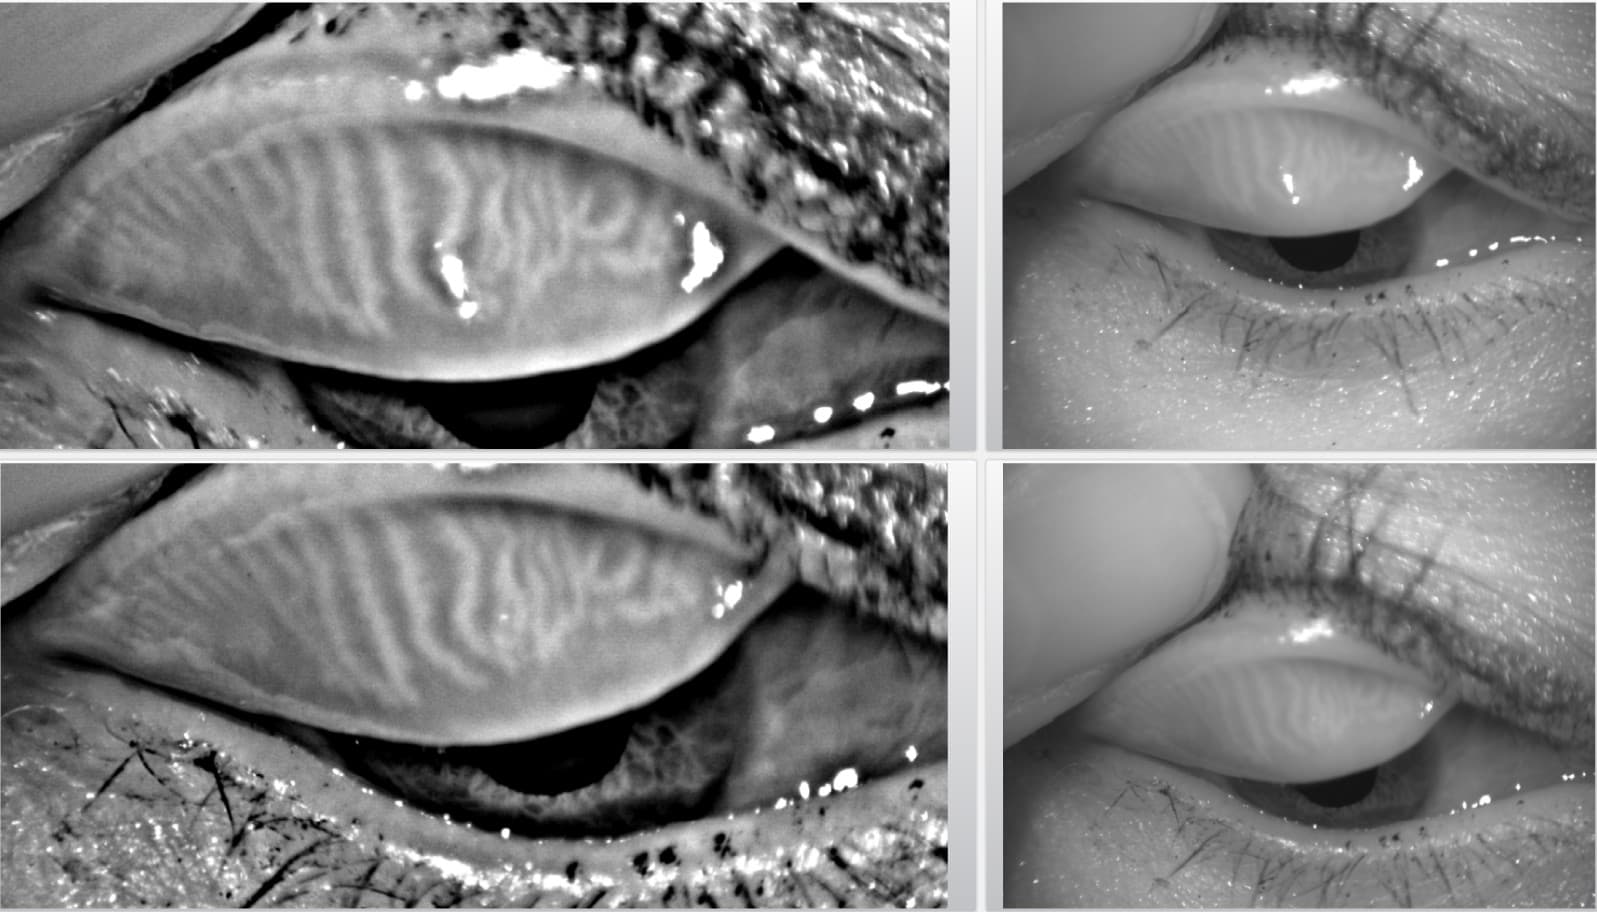

In unserer Tränensprechstunde führen wir eine umfassende Tränenanalyse durch, die verschiedene wichtige Aspekte berücksichtigt. Wir überprüfen einzelne Komponenten des Tränenfilms, analysieren die Verdunstungsrate und beurteilen, wie gleichmässig die Tränen sich auf der Augenoberfläche verteilen.

Diese umfassende Analyse hilft uns, das Problem gezielt anzugehen und die beste Lösung für Ihre trockenen Augen zu finden.